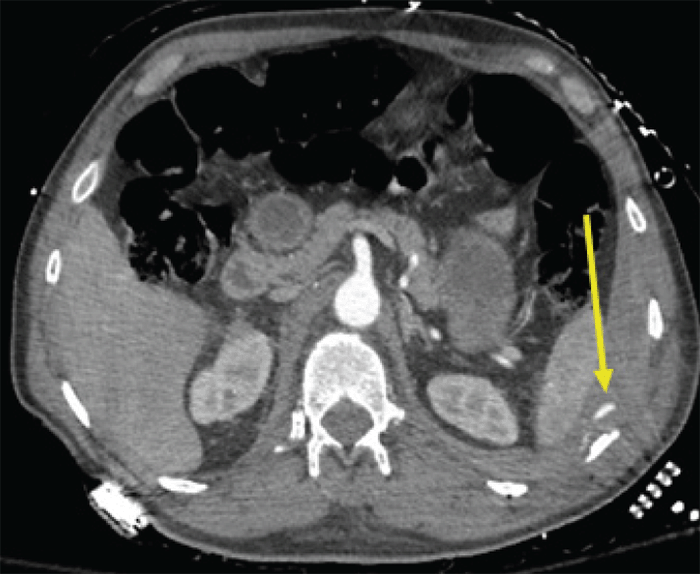

He was taken for a CT angiogram, which demonstrated an intact vascular stent, but a left hemothorax with active extravasation from a lacerated left intercostal artery at approximately the ninth rib (Figure 2).

Figure 2. Active Extravasation from Lacerated Intercostal Artery Near Fractured Left Ninth Rib. Published with Permission